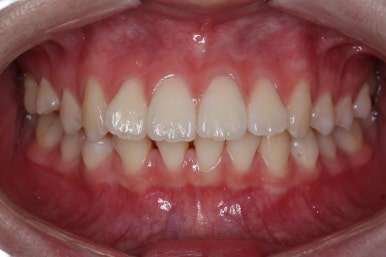

부산교정 키다리아저씨치과에서 결손치아 부분을 임플란트 하지 않고 치아교정을 통해서 개선한 이번 환자분의 치료를 마무리한 사진입니다.

치열은 가지런해졌고, 틈새는 없이 마무리되었습니다. 아랫니가 3개이지만 마치 4개인 것처럼 마무리하였고, 따라서 위~아래 치열의 중앙도 거의 맞게 마무리하였습니다.

(한 쪽은 송곳니를 앞니 대신 사용해야 했어서 크기 문제로 완벽히는 중앙을 맞추기 힘듭니다.)